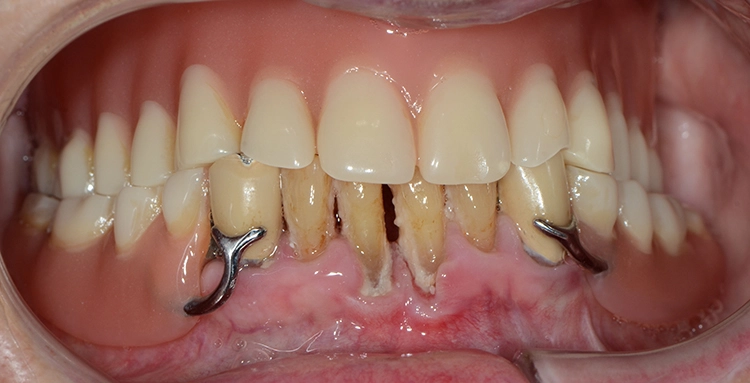

Bei den meisten alltäglichen Tätigkeiten wie Körperpflege und Kochen gaben die 100-Jährigen an, Hilfe zu benötigen. Obwohl offensichtliche Defizite in der häuslichen Mundhygiene vorlagen, wie generalisiert harte und weiche Beläge, schlecht gereinigter herausnehmbarer Zahnersatz, Druckstellen usw., gaben nur 7 (12,7%) der 100-Jährigen an, hierbei Hilfe zu benötigen. Die Abbildungen 1 bis 3 zeigen beispielhaft die klinische intraorale Situation von 3 100-Jährigen, die an der Untersuchung teilgenommen haben.